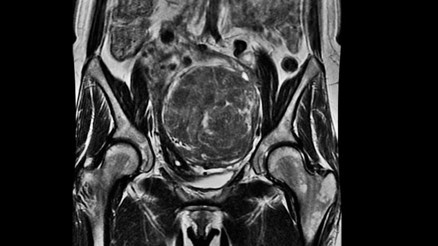

#MetamorfozMiyom, kadınlarda sık rastlanan iyi huylu bir tümördür. Peki, tümörler vücuttan alınmalı mıdır? Miyom tedavisinde rahmi korumak için en etkin yöntem hangisidir? Kadın Hastalıkları, Doğum ve Jinekolojik Onkoloji Uzmanı Doç. Dr. İlker Kahramanoğlu konu hakkında önemli bilgiler verdi.